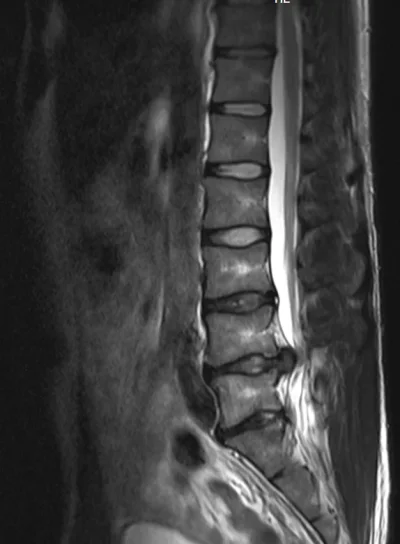

Eilisen tilanne magneetissa. Oikeasssa kankussa/lonkan seudulla ollut keväästä asti särkyä ulkokierrossa ja selällään on ollut vaikea maata. Tai oikeastaan mahdotonta niin että kankku ei olisi pienessä jännityksessä. Välillä kipu säteilee nilkkaan. Kuitenkin tuon kanssa on pystynyt elämään ja liikkumaankin kohtuullisesti.

Olen ollut sitä mieltä että kipu on lihasperäistä (tulehduksesta esim. ja liiasta autossa ja tuolilla istumisesta toimistotyöstä johtuen) ja olen sitä mieltä edelleen. Oikeastihan tuo pullistuma (joka on vasemmalla puolella) on kuvissa pahentunut, mutta vasemmalle puolelle ei kipua ole käytännössä ole ollut enää kevään jälkeen. Yksi selkä, yksi elämä. Kuvissa lokakuu 2012, maaliskuu 2013 ja joulukuu 2013.